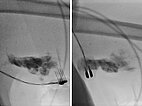

Fluoroscopy during electrosclerotherapy after injection of 0.75 mg bleomycin admixed with 2.5 ml contrast medium into the lymphatic malformation. Application of electric pulses with the finger electrode.

The same MRI (T2-weighted with fat suppression; now coronal plane) before (left) and after (right) bleomycin electrosclerotherapy. Again, it can be seen that the treated parts of the lymphatic malformation are occluded, but the remaining untreated parts are unchanged.